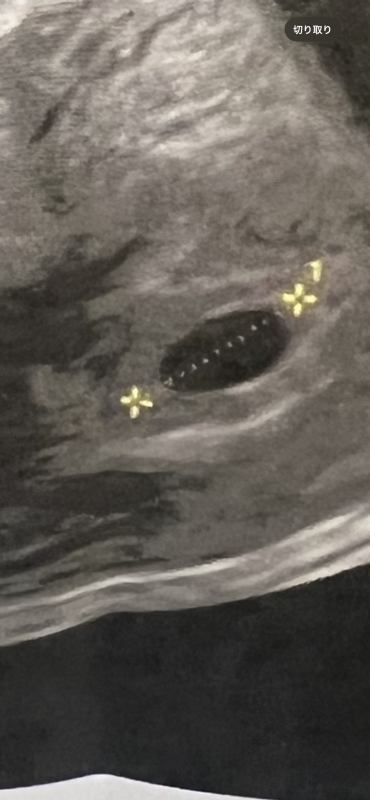

私は体外受精で5日目胚盤胞4acを移植しました!BT17に胎嚢確認でした!胎嚢14.9ミリで確認したのですが卵黄嚢が見えませんでした。先生には何も言われてないです。しかし色々調べていると14.9ミリもあって、卵黄嚢が見えてないのが不安です。体外受精なので、ズレもないと思うので、流産の確率が高いですか?

胎嚢確認のエコーも貼っときます!